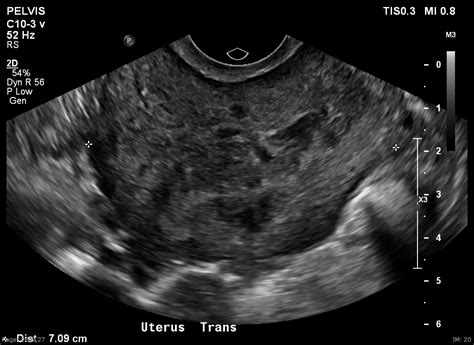

Diagnosing uterine myoma degeneration involves a combination of medical history, physical examination, and imaging tests. The diagnostic process typically includes:

• Imaging Tests: Ultrasound, MRI, or CT scans to visualize the fibroids and assess the extent of degeneration.